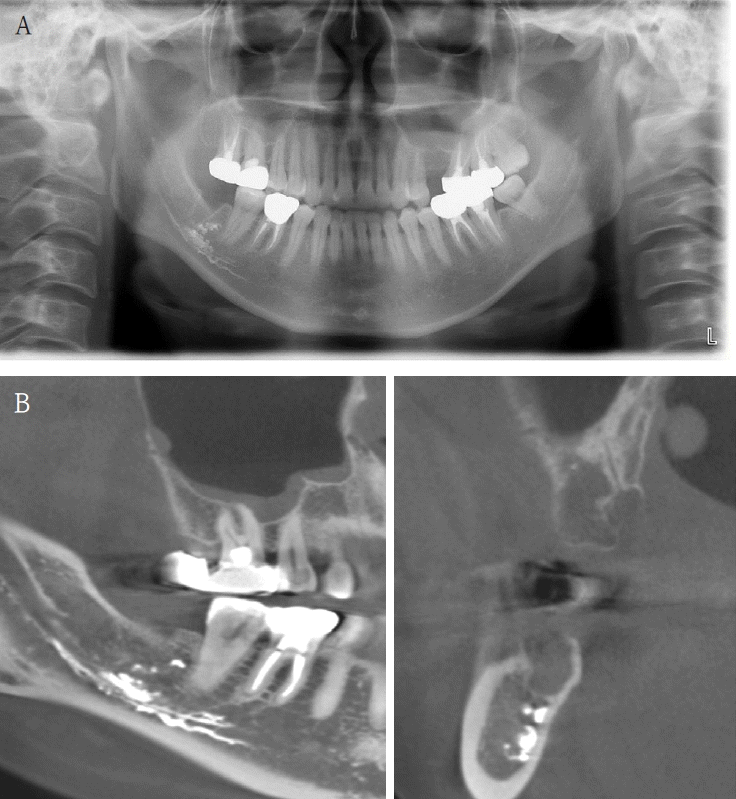

A 73-year-old male was referred after endodontic treatment of the mandibular right second molar (#47) with severe post-treatment pain. Evidence of Calcipex II extrusion into the IAN canal was evident on the panoramic radiograph and CBCT. (Fig. 8). Root canal treatment was done about 2 months ago. He underwent foreign body removal under general anesthesia (Fig. 9). Postoperatively, he reported minimal change in numbness symptoms. He was lost to follow-up but returned six months later complaining of recurrent neuropathic symptoms and itching. Carbamazepine was prescribed. No follow-up sensory testing was performed.